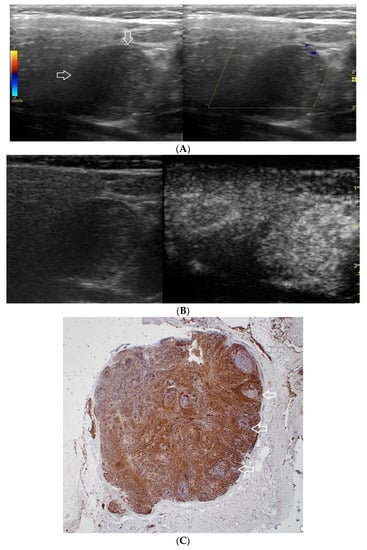

Figure 3.

(A−C) Pleomorphic adenoma. (A) Routine ultrasonographic examination in B presentation and colour Doppler: a small, well-demarcated focal lesion of a homogeneous echostructure. (white arrows). On CD, low blood flow is observed. (B) Contrast-enhanced imaging in arterial phase: a strong homogeneous enhancement of a central part of the lesion. A weakly enhanced peripheral part. (C) Pathomorphological image, immunohistochemistry for CD34. An aggregation of small vessels in central part of the lesion (white arrows).

A correlation between professional photographs of CEUS imaging and those of microscope slides containing postoperative specimens was observed. It appears that the strong heterogeneous enhancement pattern is more likely to occur in benign lesions, while malignant, and malignant potential lesions tend to present weak heterogeneous enhancement. The foundation of such tendencies is revealed in pathomorphological specimens. Various tissues such as fluid and cartilage commonly present in salivary gland tumours, are generally poorly enhanced. The enhancement of such areas in CEUS is poor if any. The cross-section of Warthin tumour, for example, is presented by one or more often numerous minor cysts containing mucus.

Those not-enhanced areas and structures revealed on histopathological photographs overlapped (Figure 1, Figure 2, Figure 3, Figure 4, Figure 5 and Figure 6).